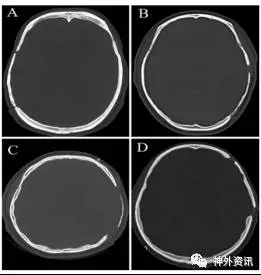

自2001年1月至2012年12月该医院为188例患者采用211块保存在聚维酮碘的冷冻自体骨瓣进行颅骨修补术。自体骨瓣取自开颅手术,用生理盐水洗净后置于无菌手套中,浸泡在0.5%的聚维酮碘溶液。经过一系列处理,注明患者姓名、性别、年龄、住院号和手术日期等,保存在-20°C的冰箱内备用。188例患者术后有8例骨瓣感染,2例在两年随访期间死亡,故将该10例剔除。其余178例患者使用201块自体骨瓣,被纳入研究。178例患者使用的201块自体骨瓣根据CT扫描显示骨瓣骨质吸收状况分成3种类型,骨瓣变薄的I型、骨瓣骨密度降低的II型和骨瓣溶解的III型(图1、2、3)。

图2. 骨瓣骨密度降低的II型:其主要特征是密度均匀下降。A和B为骨密度轻度吸收,C为骨密度中度吸收。